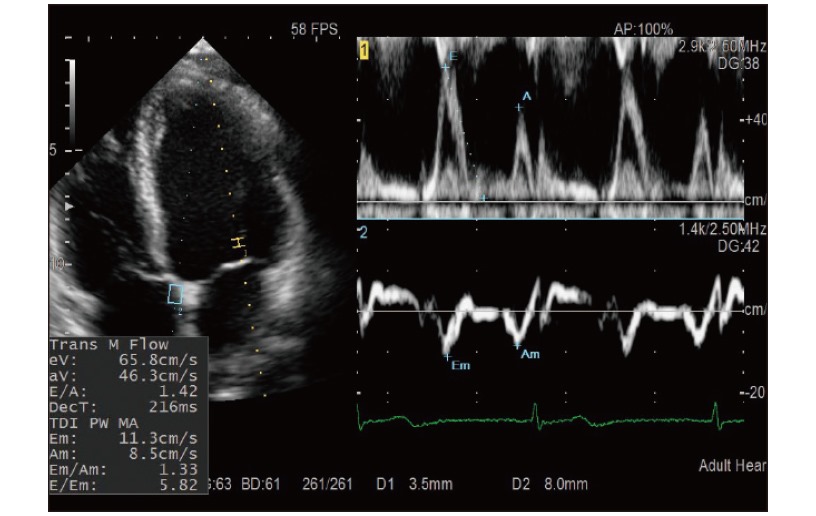

DOPPLER DE DOBLE PULSADO